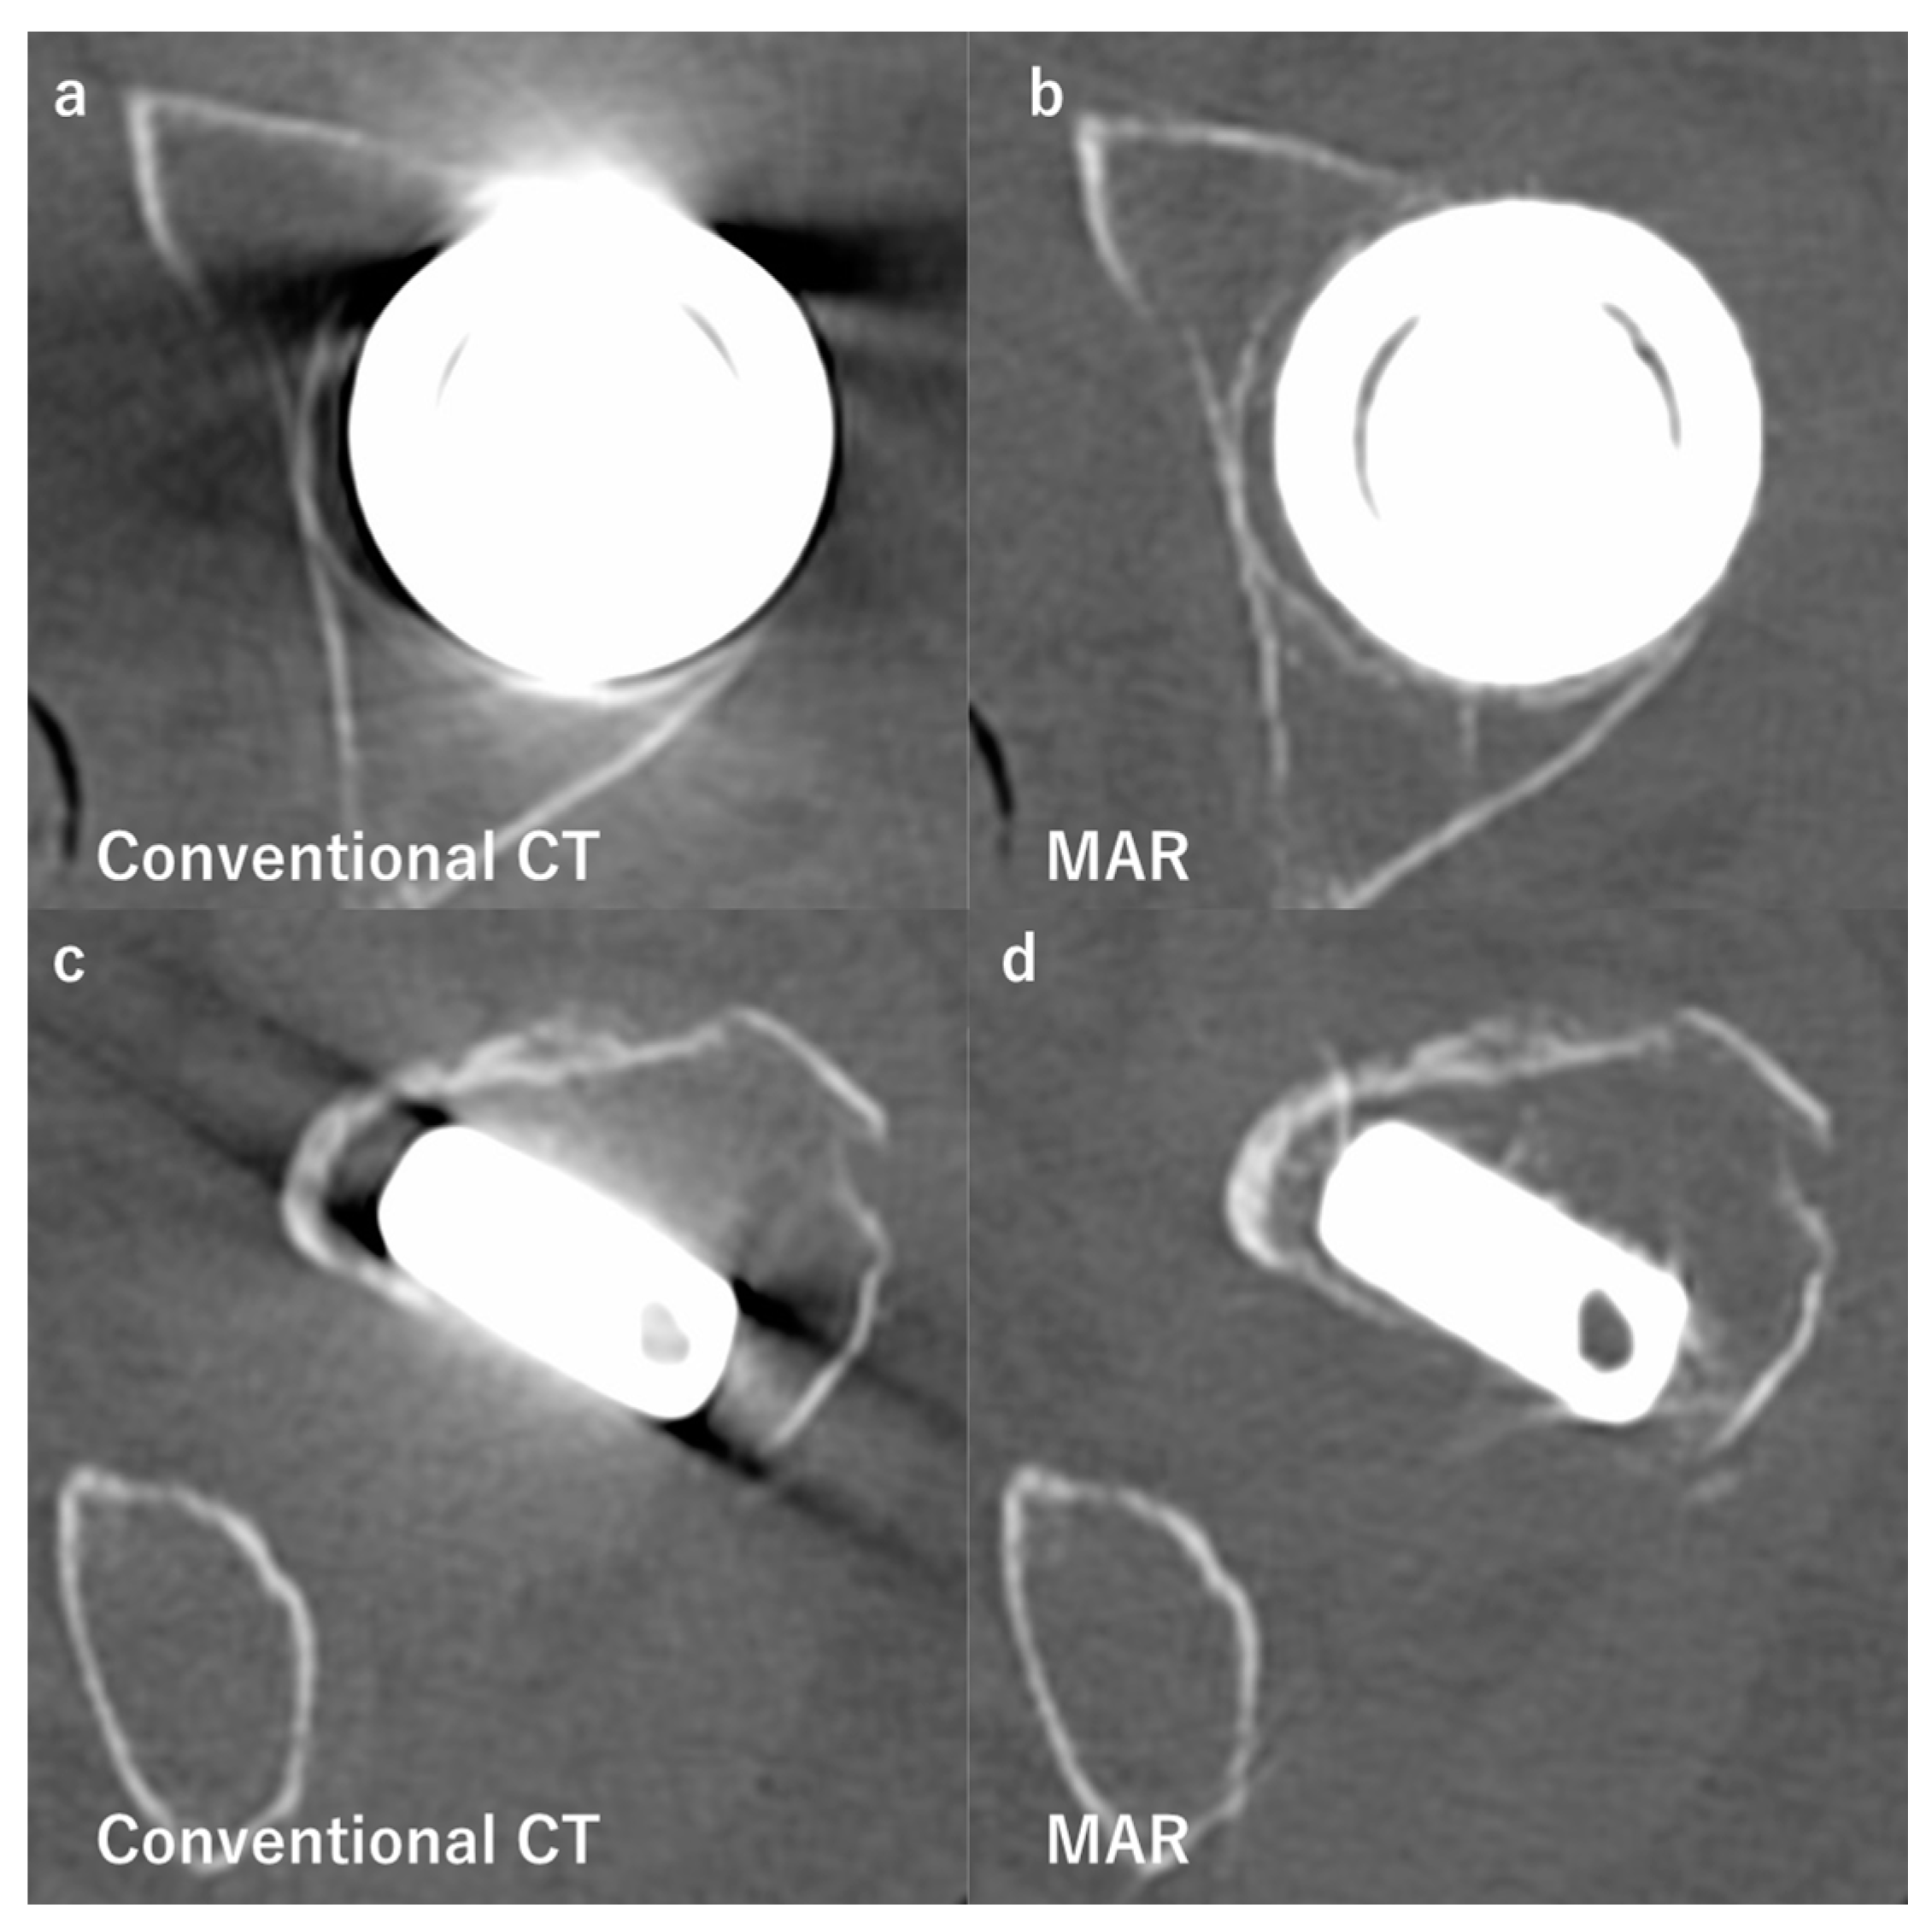

- Boomsma, M.F.; Warringa, N.; Edens, M.A.; Mueller, D.; Ettema, H.B.; Verheyen, C.C.P.M.; Maas, M. Quantitative analysis of orthopedic metal artefact reduction in 64-slice computed tomography scans in large head metal-on-metal total hip replacement, a phantom study. Springerplus 2016, 5, 405. [Google Scholar] [CrossRef] [Green Version]

- Wellenberg, R.H.H.; Boomsma, M.F.; Osch van, J.A.C.; Milles, J.; Vlassenbroek, A.; Edens, M.A.; Streekstra, G.J.; Slump, C.H.; Maas, M. Computed tomography imaging of a hip prosthesis using iterative model-based reconstruction and orthopaedic metal artefact reduction: A quantitative analysis. J. Comput. Assist. Tomogr. 2016, 40, 971–978. [Google Scholar] [CrossRef] [PubMed]

- Wellenberg, R.H.H.; Boomsma, M.F.; van Osch, J.A.C.; Vlassenbroek, A.; Milles, J.; Edens, M.A.; Streekstra, G.J.; Slump, C.H.; Maas, M. Low-dose CT imaging of a total hip arthroplasty phantom using model-based iterative reconstruction and orthopedic metal artifact reduction. Skelet. Radiol. 2017, 46, 623–632. [Google Scholar] [CrossRef] [Green Version]

- Zhang, K.; Han, Q.; Xu, X.; Jiang, H.; Ma, L.; Zhang, Y.; Yang, K.; Chen, B.; Wang, J. Metal artifact reduction of orthopedics metal artifact reduction algorithm in total hip and knee arthroplasty. Medicine 2020, 99, e19268. [Google Scholar] [CrossRef]

- Hakvoort, E.; Wellenberg, R.; Streekstra, G. Quantifying near metal visibility using dual energy computed tomography and iterative metal artifact reduction in a fracture phantom. Phys. Medica 2020, 69, 9–18. [Google Scholar] [CrossRef]